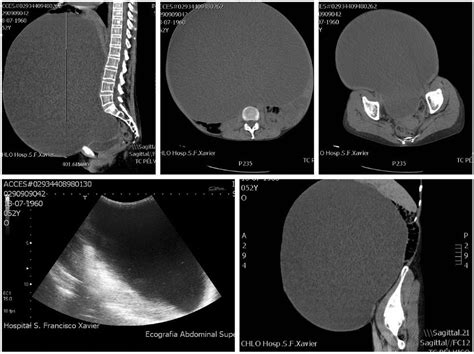

Because the symptoms of a cyst in stomach are often non-specific and mimic other digestive disorders like gastritis or ulcers, doctors rely on imaging technology to pinpoint the location and nature of the growth. Diagnosis typically follows a structured approach to differentiate between benign cysts and more serious conditions.

Ultrasound Non-invasive imaging to see if the mass is fluid-filled or solid.

CT Scan Provides detailed cross-sectional images of the abdominal organs.

MRI Offers high-contrast images, excellent for identifying tissue composition.